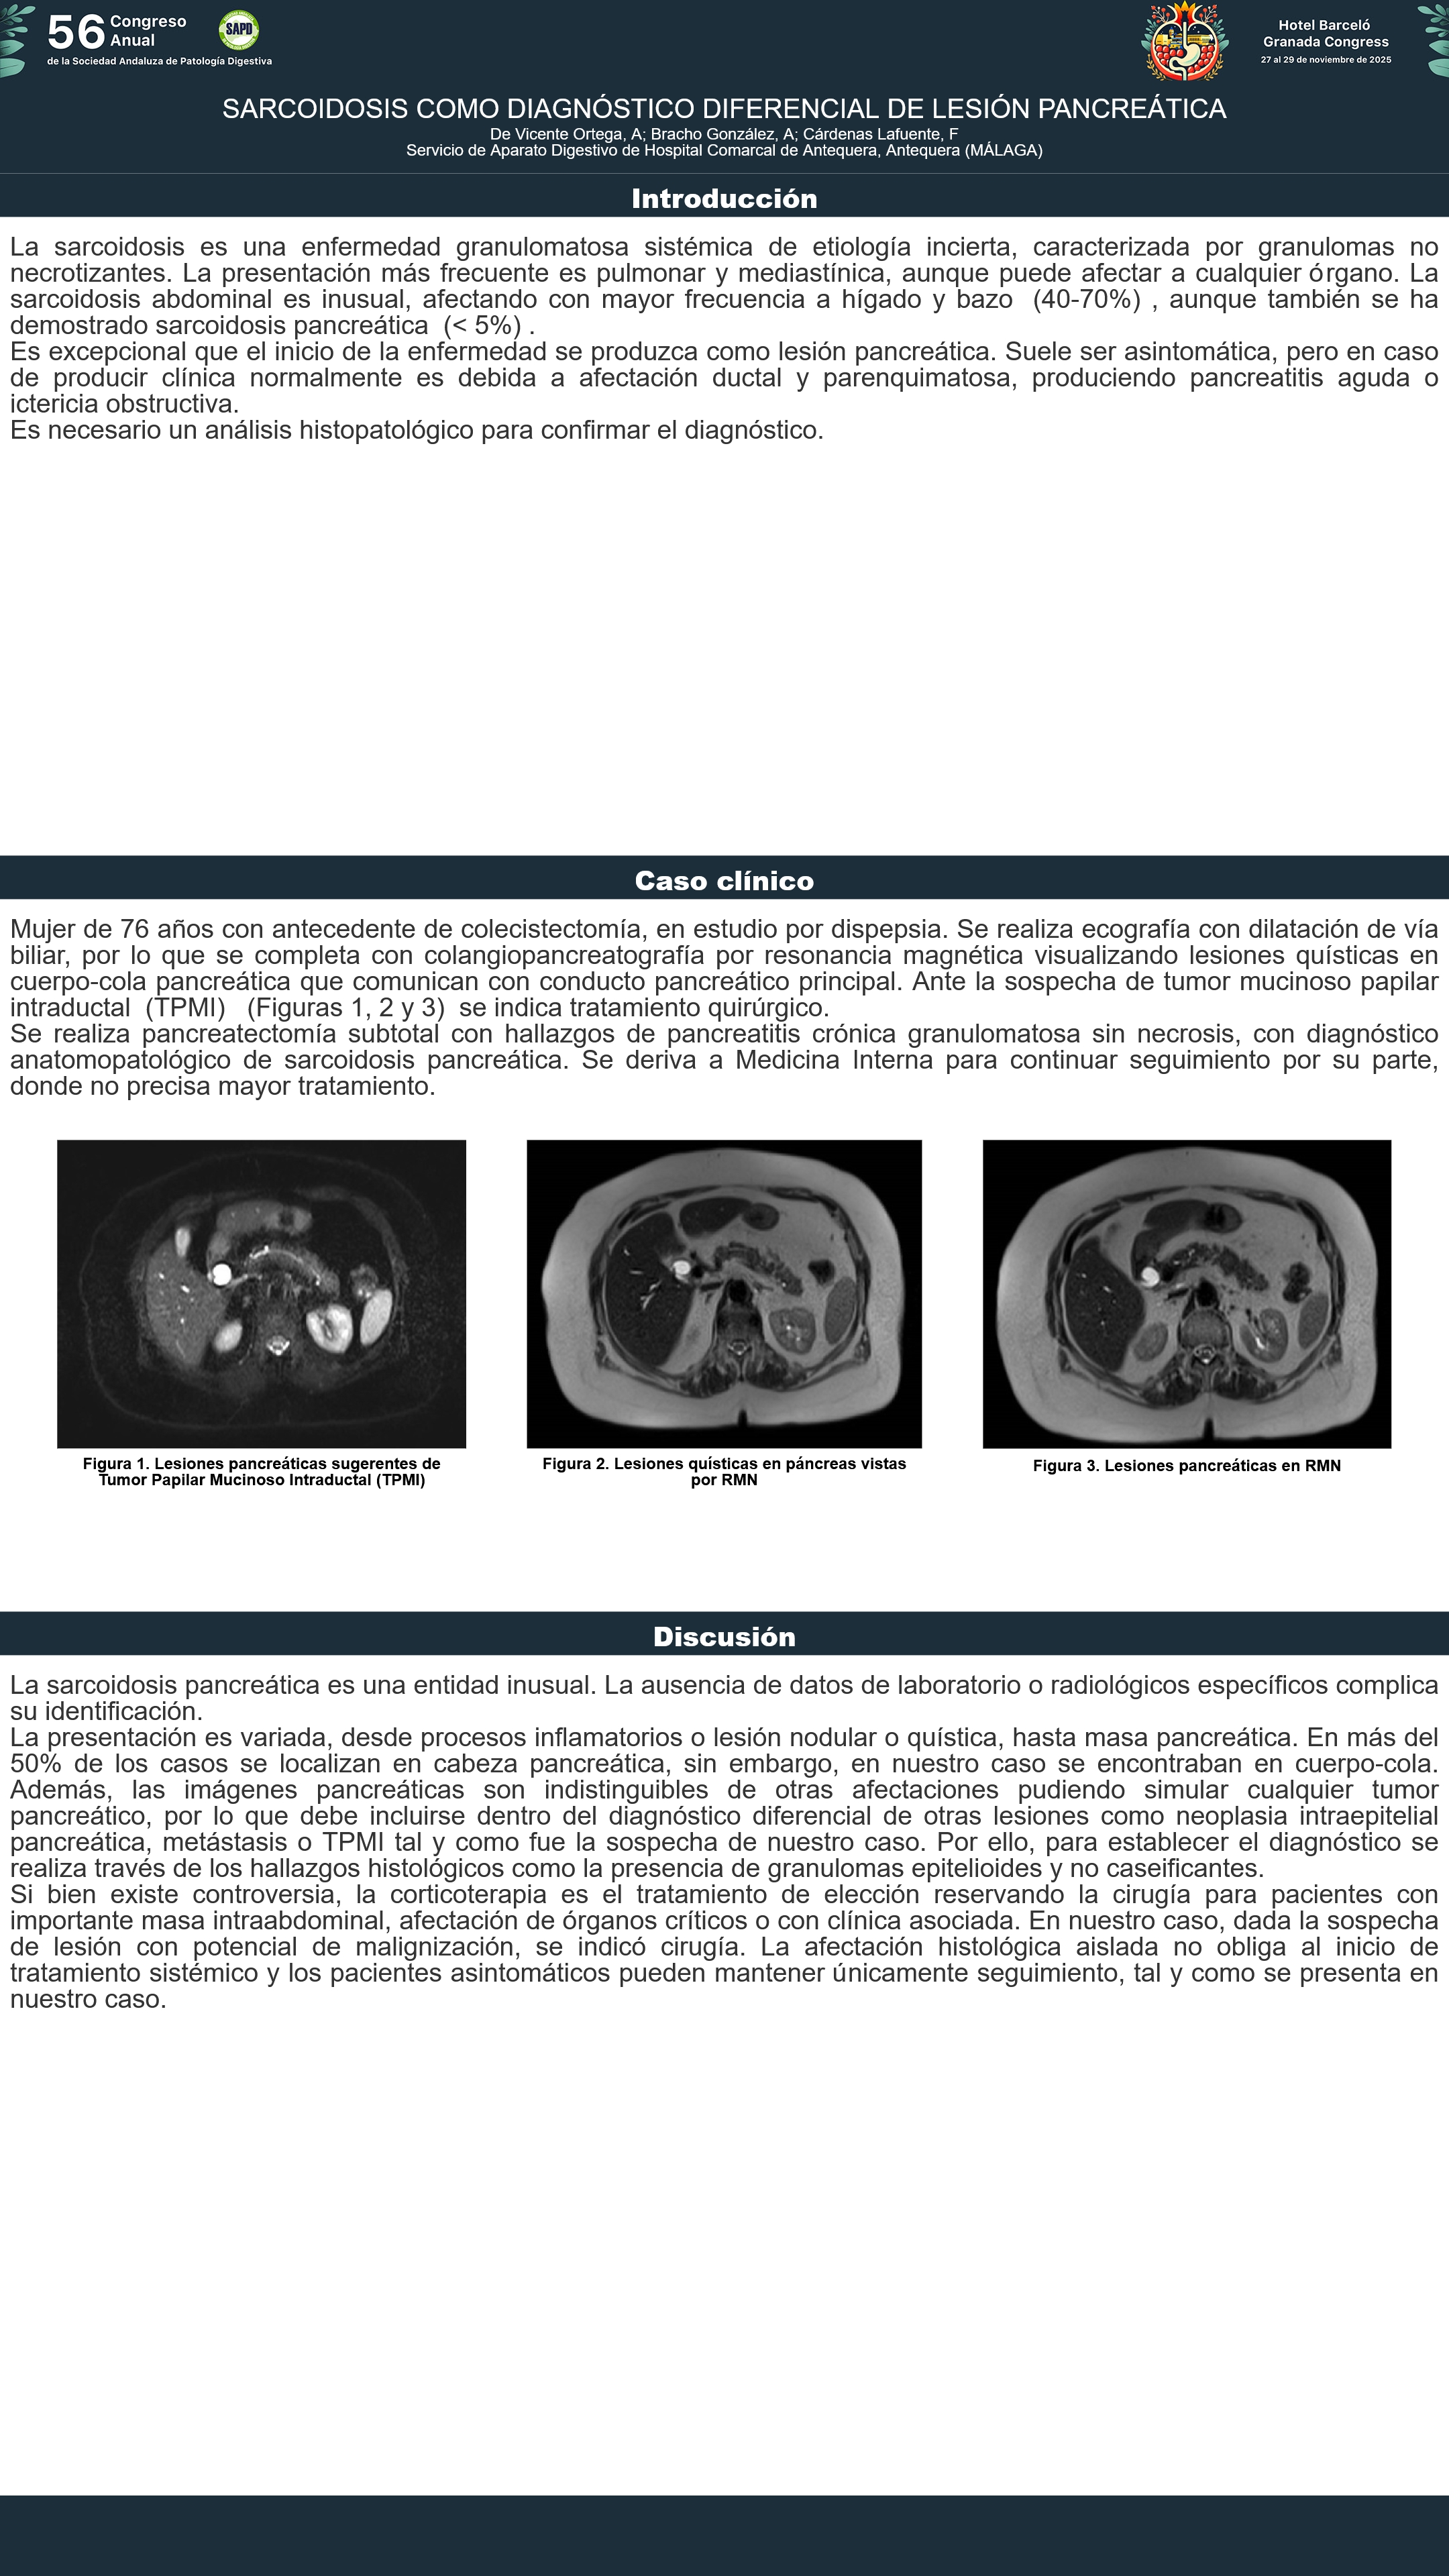

[CP-130] SARCOIDOSIS COMO DIAGNÓSTICO DIFERENCIAL DE LESIÓN PANCREÁTICA